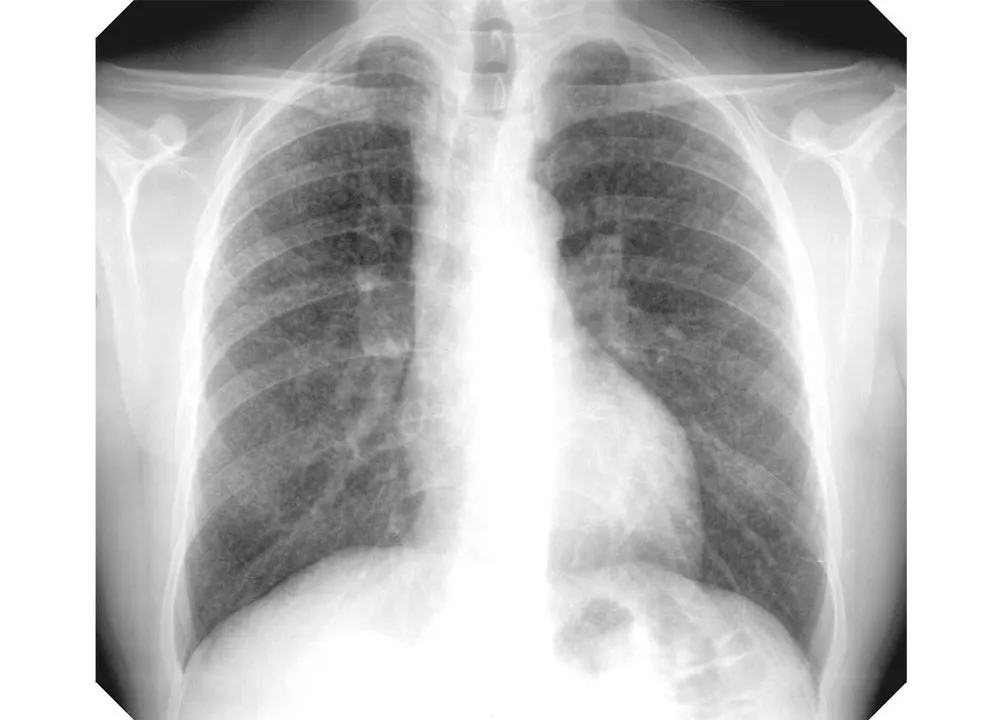

ସିଲିକୋସିସ୍ ସଂକ୍ରାନ୍ତରେ ଖଣିବହୁଳ ସୁନ୍ଦରଗଡ଼ ଜିଲ୍ଲାରୁ ଚମକାଇ ଦେଲା ଭଳି ତଥ୍ୟ ସାମନାକୁ ଆସିଛି। ୨୦୧୫ରୁ ୨୦୧୯, ୫ ବର୍ଷ ମଧ୍ୟରେ ଜିଲ୍ଲାରେ ଏହି ରୋଗରେ ଆକ୍ରାନ୍ତଙ୍କ ସଂଖ୍ୟା ୭୨୬୯୫ ଥିବା ସ୍ବାସ୍ଥ୍ୟ ବିଭାଗର ରିପୋର୍ଟ କହୁଛି। ତଥ୍ୟାନୁସାରେ, ୨୦୧୫ରେ ବର୍ହିବିଭାଗରେ ୧୦୯୯୭, ୨୦୧୬ରେ ୧୩୧୨୪, ୨୦୧୭ରେ ୧୭୦୮୪, ୨୦୧୮ରେ ୨୦୭୫୦, ୨୦୧୯ରେ ୧୦୭୪୦ ସିଲିକୋସିସ୍ ଲକ୍ଷଣ ଥିବା ରୋଗୀ ଆସିଥିଲେ। ସେହିପରି ଜିଲ୍ଲାର ଡାକ୍ତରଖାନାଗୁଡ଼ିକରେ ୫ ବର୍ଷରେ ୨୬୩ ଜଣ ରୋଗୀ ଚିକିତ୍ସିତ ହୋଇଥିବା ତଥ୍ୟ ରହିଛି। ୨୦୧୫ରେ ୨୯, ୨୦୧୬ରେ ୩୯, ୨୦୧୭ରେ ୧୨୨, ୨୦୧୮ରେ ୬୩ ଓ ୨୦୧୯ରେ ୧୦ ଜଣ ରୋଗୀ ଚିକିତ୍ସିତ ହୋଇଥିଲେ। ତେବେ ଆଶ୍ଚର୍ଯ୍ୟଜନକ ଭାବେ ତା’ ପରବର୍ଷ ଅର୍ଥାତ୍ ୨୦୨୦ ରିପୋର୍ଟରେ ରୋଗୀ ସଂଖ୍ୟା ଶୂନ ରହିଛି। ସିଲିକା ନାମକ ଏକ ଗୁଣ୍ଡ ଯୋଗୁ ହେଉଥିବା ସିଲିକୋସିସ୍ ରୋଗ ଫୁସଫୁସକୁ ଆକ୍ରାନ୍ତ କରିଥାଏ। ବିଶେଷ କରି ପଥର, ସୁନାଖଣି, ଚୂନପଥର, କାଚ, କୋଇଲା ଖଣି ସମେତ ସିମେଣ୍ଟ କାରଖାନାର ଶ୍ରମିକମାନେ ଏଥିରେ ଆକ୍ରାନ୍ତ ହୋଇଥାନ୍ତି। ସୁନ୍ଦରଗଡ଼ରେ ଉପରୋକ୍ତ ଖଣି କାରଖାନା ରହିଥିବାରୁ ସିଲିକୋସିସ୍ ଆକ୍ରାନ୍ତଙ୍କ ସଂଖ୍ୟା ଏଠାରେ ଅଧିକ। କିନ୍ତୁ ସ୍ବାସ୍ଥ୍ୟ ବିଭାଗ ଏହାକୁ ସେତେଟା ଗୁରୁତ୍ବ ଦେଉ ନଥିବା ଅଭିଯୋଗ ହେଉଛି। ଜିଲ୍ଲା ମୁଖ୍ୟ ଚିକିତ୍ସା ଓ ଜନସ୍ବାସ୍ଥ୍ୟ ଅଧିକାରୀ ଡ. ସୁରେଶଚନ୍ଦ୍ର ମହାନ୍ତି କହିଛନ୍ତି ସିଲିକୋସିସ୍ ରୋଗ ଚିହ୍ନଟ ବା ଚିକିତ୍ସା ବ୍ୟବସ୍ଥା ନଥିବାରୁ ଏ ସମ୍ପର୍କରେ ଜାଣିବା ମୁସ୍କିଲ।